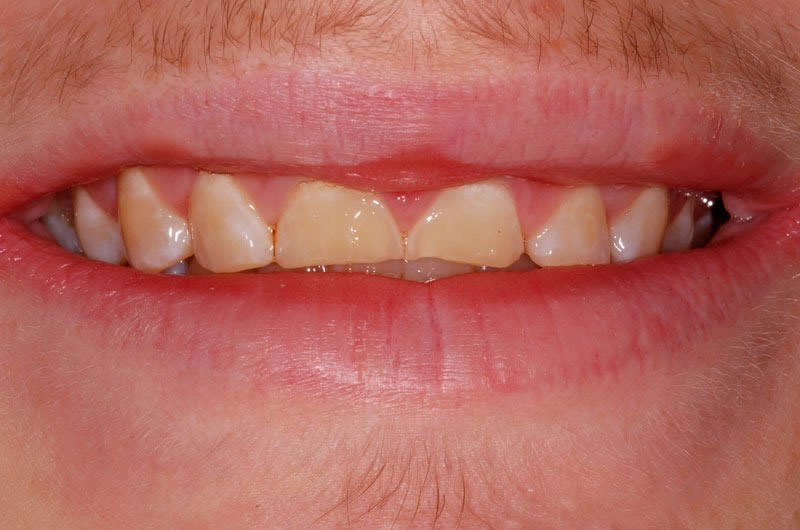

Case Studies

Dental Crowns (7 images)